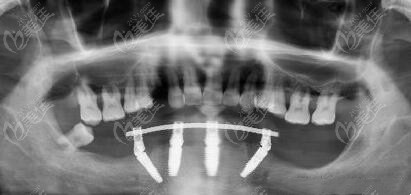

合肥佳冠口腔种牙怎么样,据说何初华做全口all-on-4种植牙技术有名气 b820 G0 V0

合肥佳冠口腔何初华医生种牙好不好?找他做全口all-on-4种植牙靠谱吗?有谁在他那里做过......